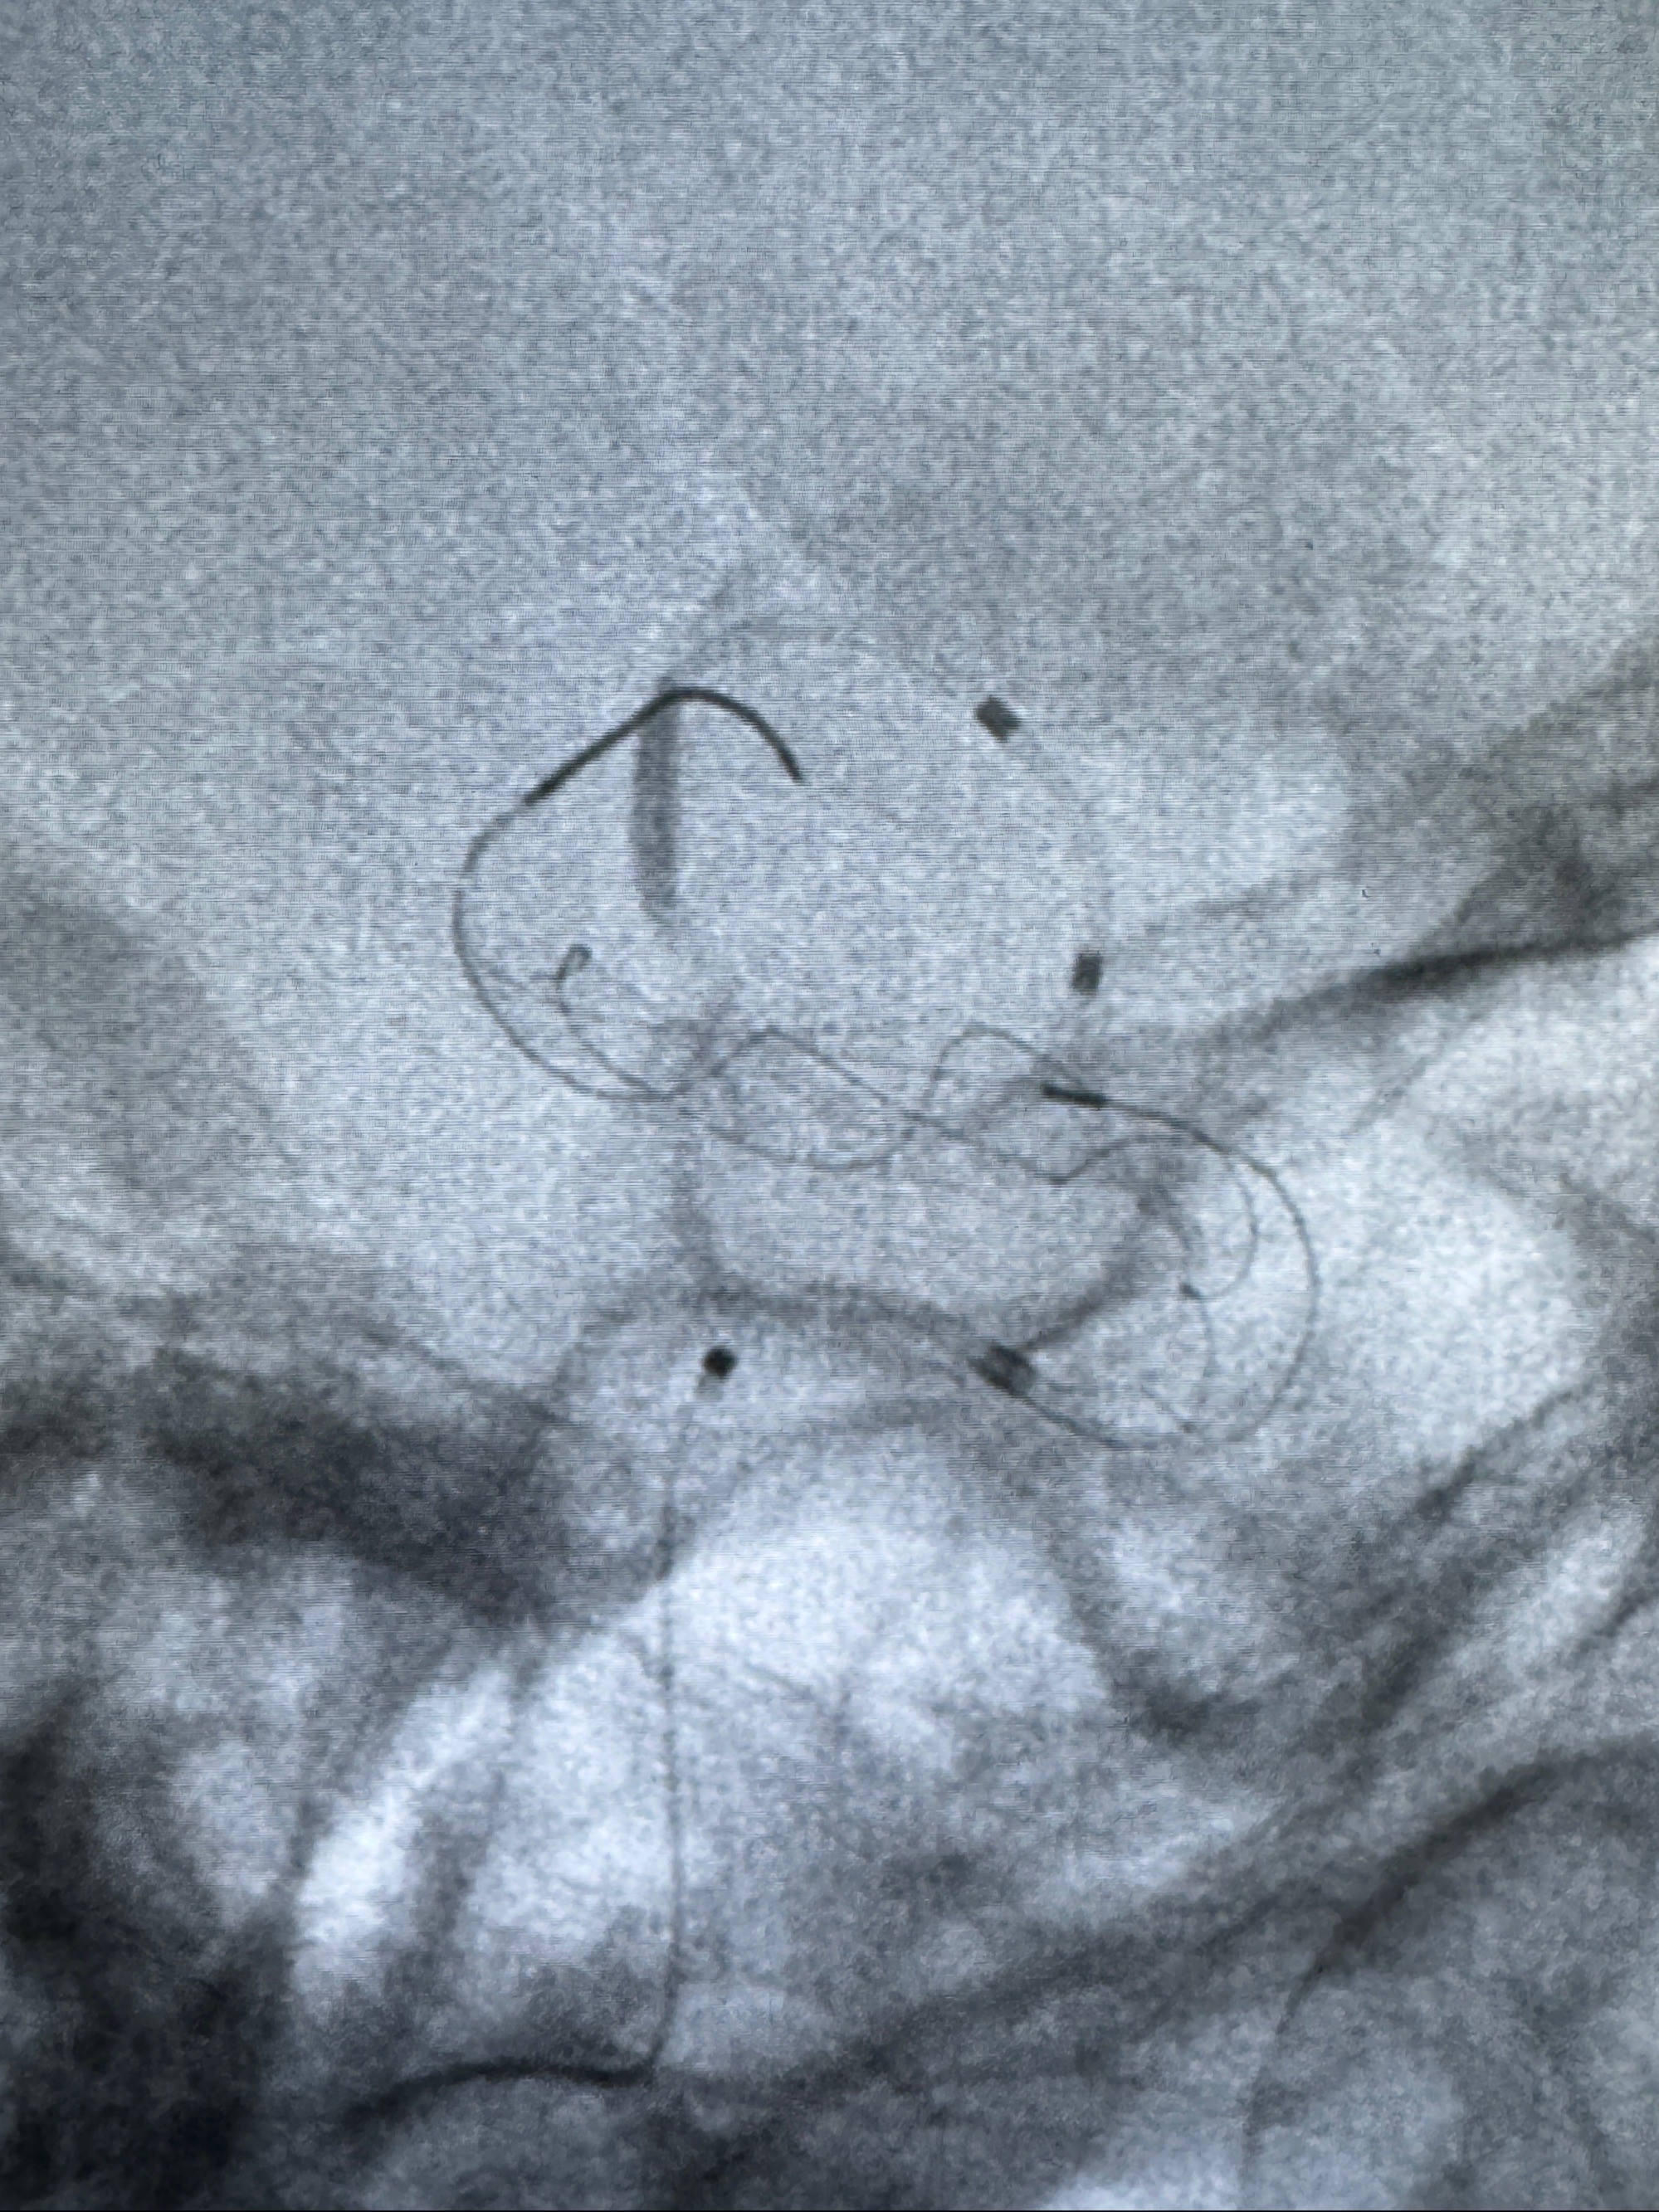

透视可见红圈部分为支架导管的头端

手推冒烟显示支架位置及展开情况,箭头为支架导管的位置

尝试回收支架失败,只能考虑释放支架了

逐帧图像展示歪着脖子释放支架,旁边吩咐助手手机摄影、拍照留像(透视机不能留影像)

接下的视频为释放支架的过程及试图确认支架与血管的关系

最后再看看颅内血管是否有异常

看动脉瘤内造影剂滞留,未见明确射流,遂撤出预留的栓塞微导管,快速结束手术,经导引导管灌注替罗非班250ug。